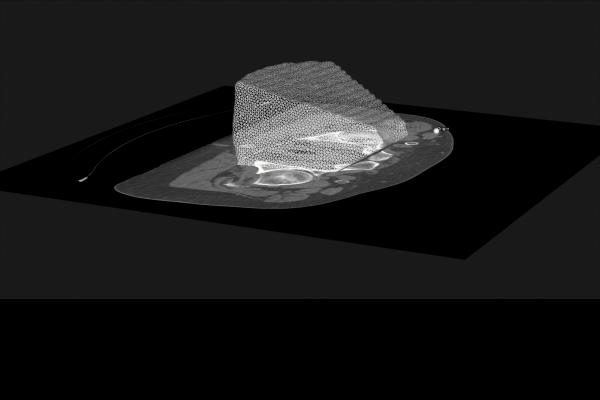

- The Use of Hybrid Imaging in Radiotherapy Treatment Planning